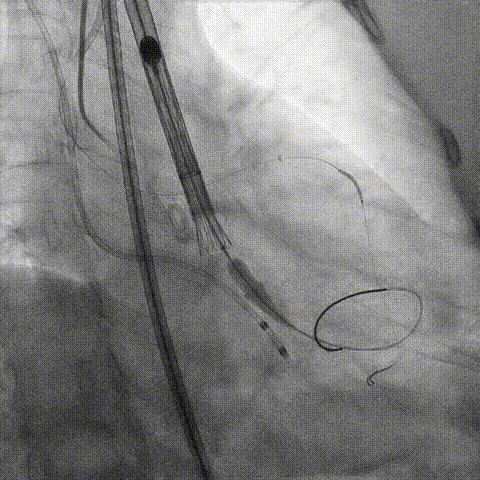

释放冠脉支架

释放瓣膜

造影评估

支架内后扩张

冠脉造影

根部造影

最终结果